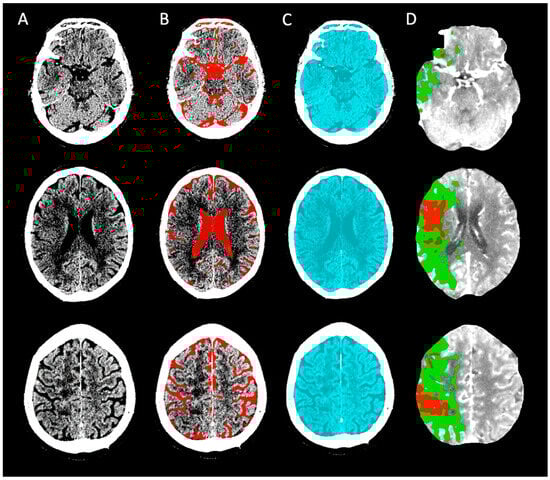

2.2. Baseline Image Acquisition, Post-Processing, and Quality Assessment

2.3. ICV and Cerebrospinal Fluid (CSF) Assessment